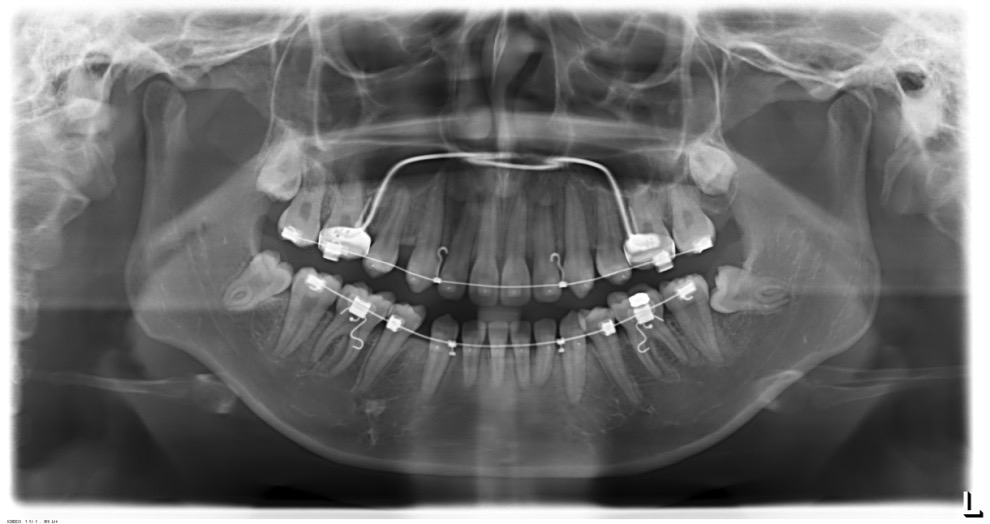

全景片

牙根基本平行,未见牙根吸收